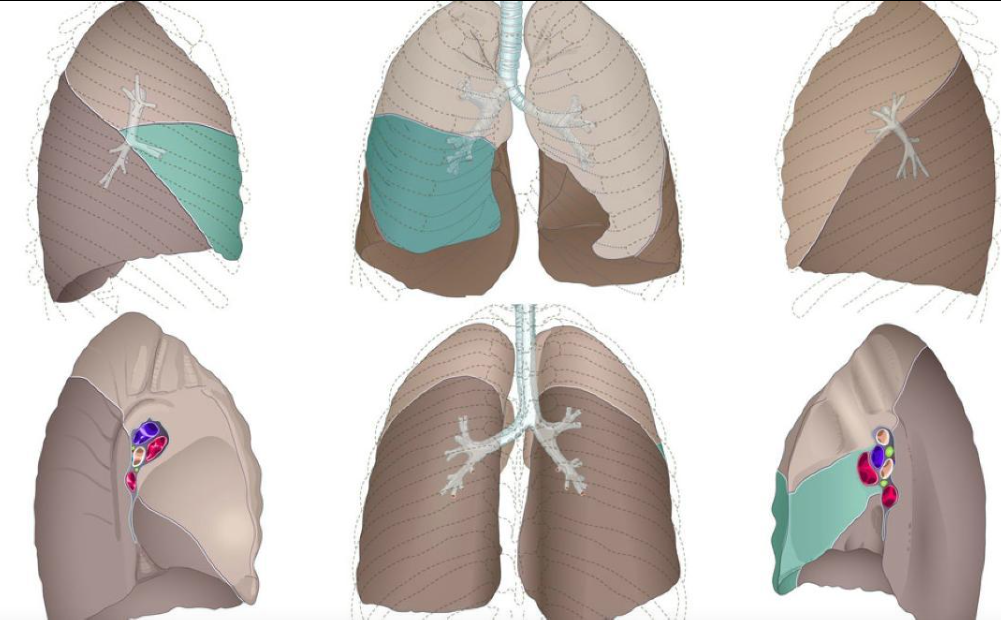

Lóbulos pulmonares IMAGEN

A